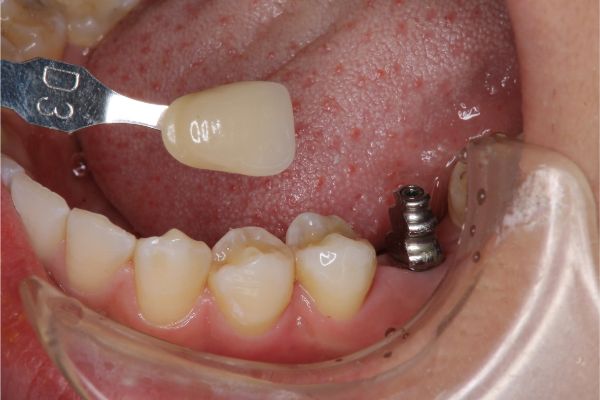

照相比色